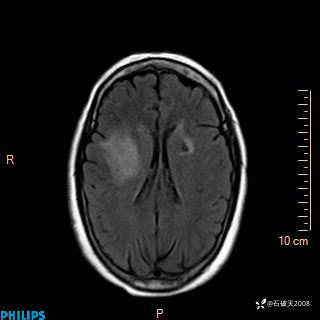

2024.2.21MR

DWI

ADC

增强轴位

增强冠状位

增强矢状位